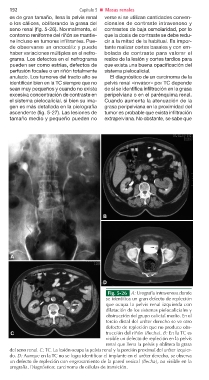

Fig. 5-26 A: Urografía intravenosa donde

se identifica un gran defecto de repleción

que ocupa la pelvis renal izquierda con

dilatación de los sistemas pielocaliciales y

obstrucción del grupo calicial medio. En el

tercio distal del uréter derecho se ve otro

defecto de repleción que no produce obs-

C trucción del riñón (flecha). B: En la TC es

visible un defecto de repleción en la pelvis

renal que llena la pelvis y oblitera la grasa

del seno renal. C: TC. La lesión ocupa la pelvis renal y la porción proximal del uréter izquier-

do. D: Aunque en la TC no se logra identificar el implante en el uréter derecho, se observa

un defecto de repleción con engrosamiento de la pared vesical (flecha), no visible en la

urografía. Diagnóstico: carcinoma de células de transición.